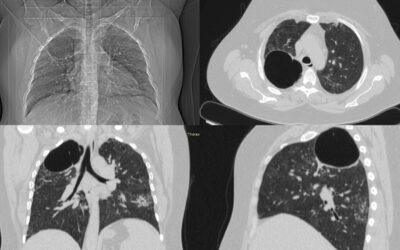

ტრაქეის და მარჯვენა მთავარი ბრონქის არაწვრილუჯრედოვანი კარცინომის ლაზერული რეზექცია

პაციენტი 60 წლის მამაკაცი, დიაგნოსტირებული არაწვრილუჯრედოვანი კარცინომით. სიმსივნური პროცესი გავრცელდა მარცხენა მთავარ ბრონქში და ტრაქეის ქვედა მესამედზე, რამაც გამოიწვია პაციენტის კლინიკური მდგომარეობის კრიტიკული დამძიმება, რაც გამოიხატა ჰაერის ძლიერი უკმარისობით,...